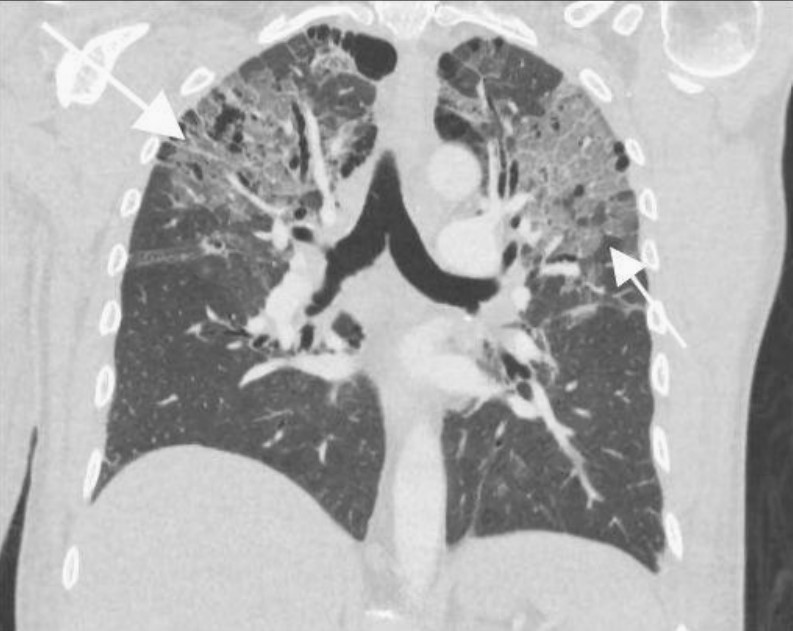

患者左下肢X線片顯示腓骨和脛骨骨折。胸片顯示上肺葉雙側(cè)肺泡混濁,這些不明確的斑片狀氣腔模糊是非特異性的,可見于肺水腫、誤吸或感染。繼續(xù)為患者行胸部CT檢查,CT顯示肺動脈干、左或右肺動脈主干或肺葉動脈無充盈缺損,雙側(cè)胸腔積液。肺窗顯示雙側(cè)上、左中肺野斑片狀磨玻璃影伴小葉間隔增厚。

鑒于患者的骨折和呼吸困難,考慮肺脂肪栓塞。與肺脂肪栓塞相關(guān)的最常見CT結(jié)果包括局灶性或彌漫性磨玻璃影、片狀或彌漫性實變區(qū)以及各種小結(jié)節(jié)(<10 mm)。罕見觀察到肺動脈內(nèi)脂肪衰減充盈缺損。患者最終診斷為肺脂肪栓塞。

圖2 冠狀位CT顯示位于雙上肺野和左中肺野的斑片狀磨玻璃影伴小葉間隔增厚(白色箭頭)